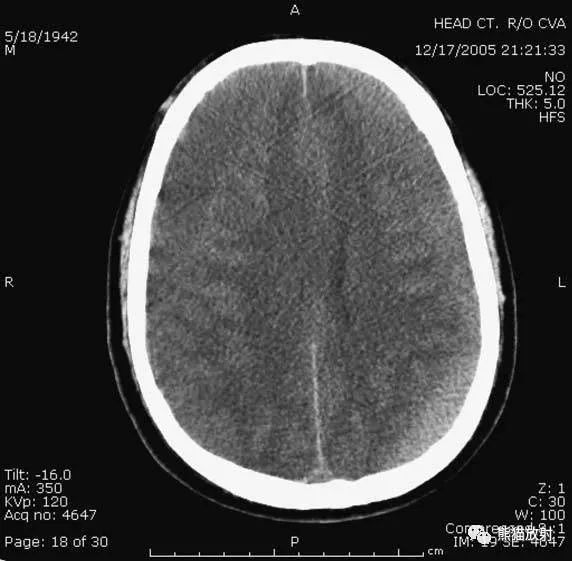

6、脑梗死

缺血性脑卒中早期:脑水肿,灰白质分界模糊,脑沟消失;

中期:病变区域密度减低;

晚期:脑实质体积缩小。

A:陈旧性脑梗死,右枕叶体积缩小;

B:左枕叶急性脑梗死,灰白质分界模糊,脑沟消失;